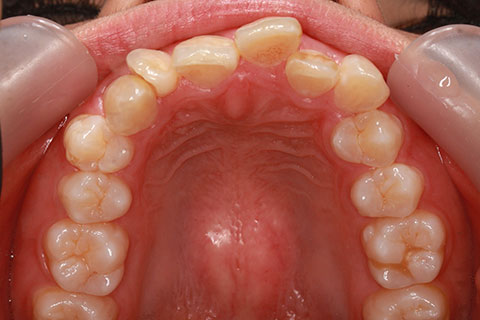

治療後

- 年齢・性別

- 25歳女性

- 治療期間

- 2年0ヶ月

- 抜歯

- 上下4番抜歯

- 治療費

- 110万円

- 表側矯正と比較して、力学的な操作性が複雑なため、ボーイングエフェクトを起こしやすい。